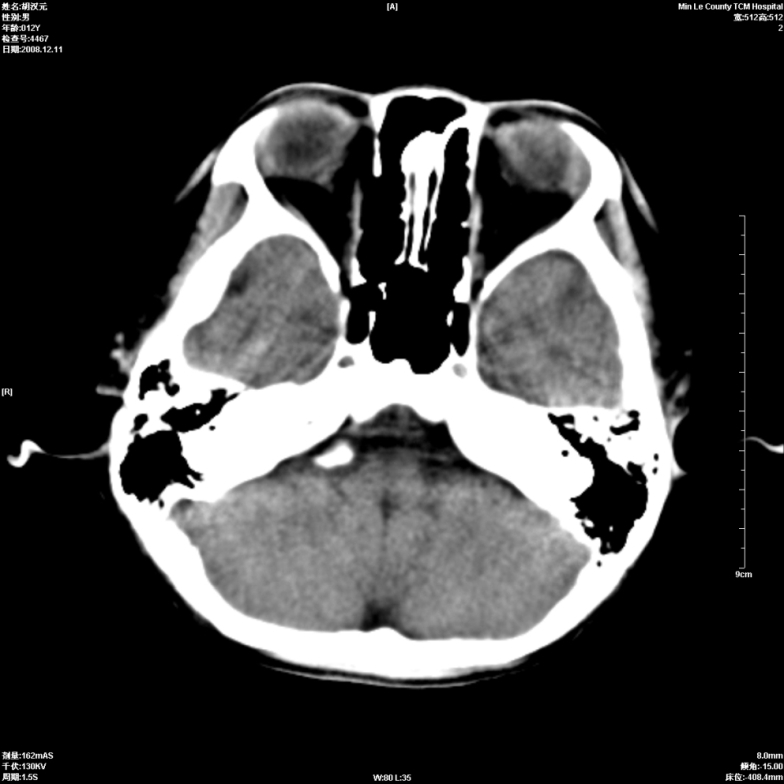

标题: PED1681:头疼发热约一周 [打印本页]

标题: PED1681:头疼发热约一周

颅脑未见确切异常。必要时进一步检查,如mri、脑脊液检查。

两侧顶部近灰质处白质密度降低,是否炎性改变

颅脑ct轴位平扫颅内未见明确异常;建议必要时复查或行进一步检查。

两侧顶部近灰质处白质密度降低,建议mri